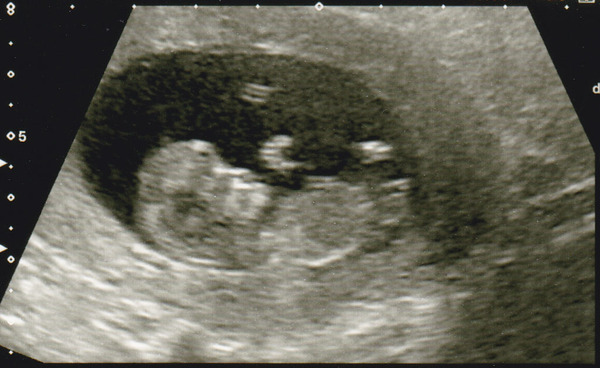

Admitting to have lurked for a little while, but following a miscarriage back in April wouldn't let myself join in until I'd had the dating scan. Which was today.

Had a lovely radiographer who picked up how nervous I was, and did a fabulous job. Told him why I was nervous, and he spent loads of time showing and explaining all the bits of little wiggle that we could see.

EDD 30th March... DD was 2 weeks over her date... OH is hoping Wiggle will be a couple of weeks early and arrive on his birthday - we'll see!

11w 2d..... and just starting to feel like I can breathe again....

Welcome Reiki scan picture is so cute :)